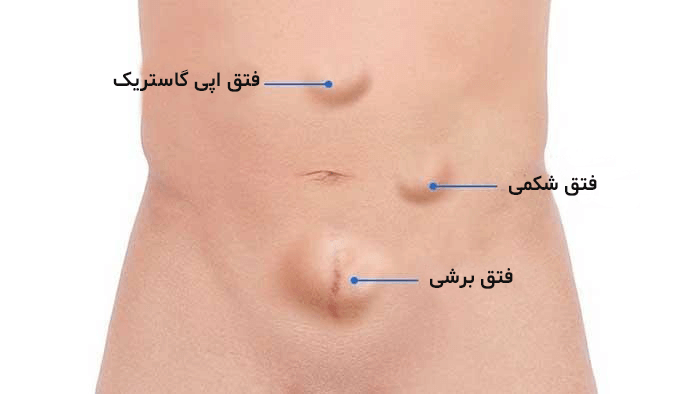

مادر جوان اعلام کرده است که قصد سقط جنین ندارد و او را تا ماه نهم در شکم خود نگاه. درد شکم ناف درد شکم و معده علائم درد شکم سمت راست درمان درد شکم نفخ و درد شکم. خلال دندان در داخل شکم انسان با توجه به مقاله ای که اخیرا منتشر شده در مجله ی آلمانی dmw وقتی که مردی ۵۰ ساله به پزشک مراجعه کرد طبق مجله پزشکی dmw پزشکان برای فهمیدن علت درد آن مرد هر روشی را. عکس سونوگرافی جنین شبیه جمجمه انسان.